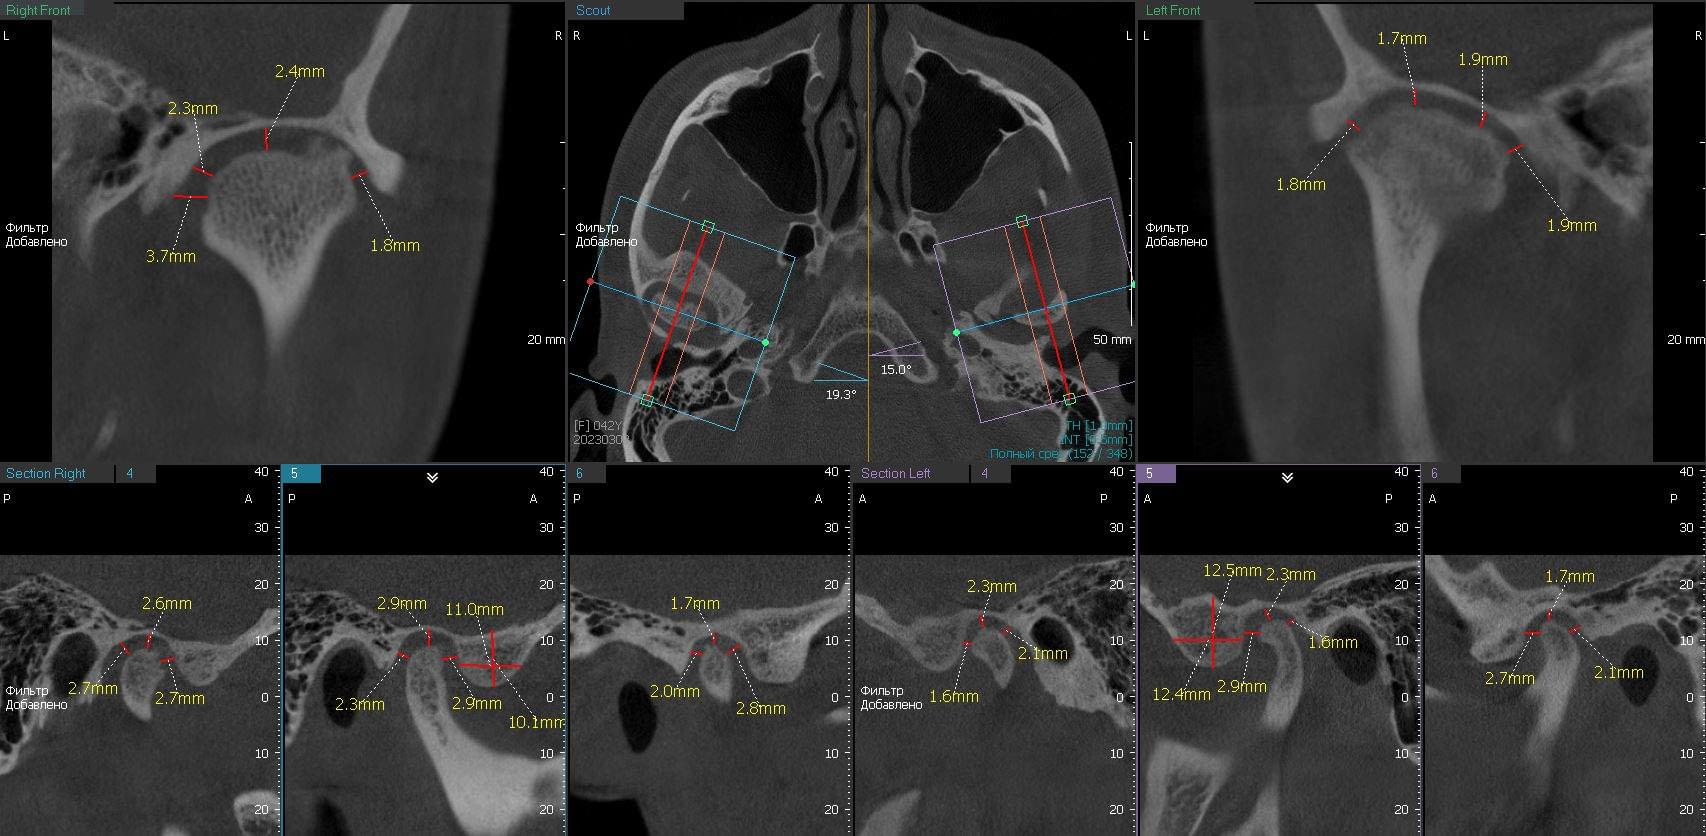

Дисфункція скронево-нижньощелепного суглобу

Якщо ви маєте сумніви щодо свого скронево-нижньощелепного суглобу, компанія MyRay Lab є вашим надійним партнером у діагностиці та визначенні причин цієї дисфункції. Ми спеціалізуємося на проведенні КТ-досліджень суглобів, черепа та навколишніх тканин, що дозволяє нам докладно оцінити структуру та функцію скронево-нижньощелепного суглобу.

Однією з головних переваг співпраці з MyRay Lab є наша високотехнологічна устаткування, що використовується в процесі КТ. Ми застосовуємо передові технології, які забезпечують зображення високої якості та дозволяють отримати детальну інформацію про стан суглобу. Наша компанія MyRay Lab використовує інноваційні методи та підходи, щоб допомогти нашим клієнтам у точному діагностуванні та розумінні проблем щодо їх скронево-нижньощелепного суглобу.

Здоров'я наших клієнтів є нашим пріоритетом, тому ми пропонуємо індивідуальний підхід до кожного пацієнта, що звертається до нас для діагностики дисфункції скронево-нижньощелепного суглобу. Наші досвідчені фахівці використовують комбінацію клінічного дослідження та КТ-сканування, щоб з'ясувати причини симптомів та розробити ефективний план лікування.